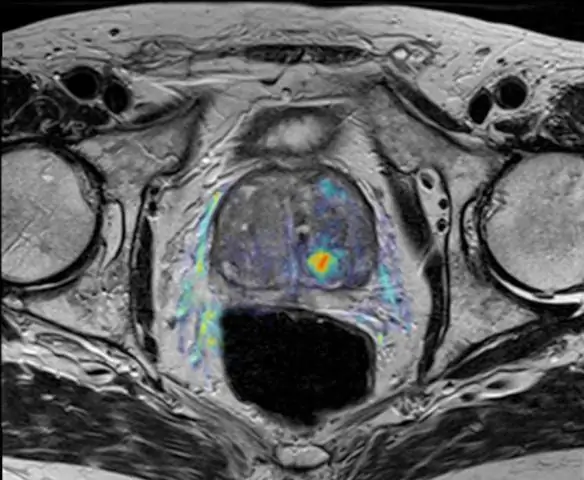

У вас будут те же тесты, которые вы должны пройти для диагностики множественной миеломы в первую очередь, например, анализы крови и мочи. Вам также могут понадобиться дополнительные визуализирующие исследования или повторная биопсия костного мозга.